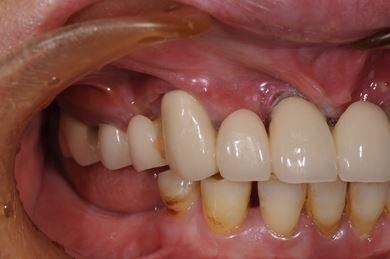

インプラントの症例写真 IMPLANT

インプラント治療+セラミック治療

| 主訴 | 上の奥歯がむし歯で治したい。下の歯が少ないので、インプラントか入れ歯、できれば併用で。 | ||||||||||||||||||||||||||||||||

| 治療方針 | インプラント治療にて、機能的・審美的回復を行う。 | ||||||||||||||||||||||||||||||||

| 治療内容 | インプラント3本、ハイブリッドセラミッククラウン5本 | ||||||||||||||||||||||||||||||||